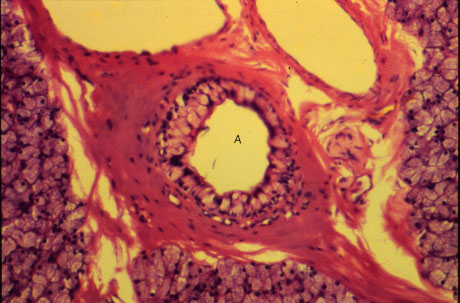

K-slide 59:

A. Interlobular duct. Note that most of the cells making up its wall are goblet cells.